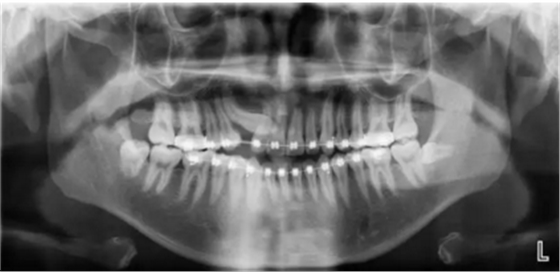

這些逆襲的牙齒真的沒(méi)辦法嗎?。。。

第一種方法:糾正過(guò)來(lái)!

第二種方法:干掉它!

第三種方法:不管它唄!

阻生齒外科聯(lián)合正畸治療